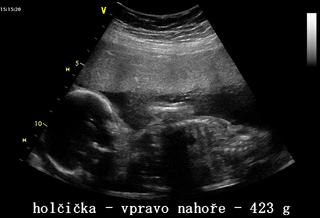

Ahoj holky.Delší dobu jsem se neozvala,ale napravuji to.Dnes jsme byli na tom velkém utz.

No a máme potvrzené dvě holčičky.A mělo by být vše v pořádku.Když budete chtít,mrkněte na fotky.

Teda jedna potvůrka byla otočená,takže obličejík neukázala.Tak snad příště.

@martasl Nikolce se to splnilo.Byla nadšená.Zato přítel.Prej je to na provaz mít doma 4 ženský 😀 😀